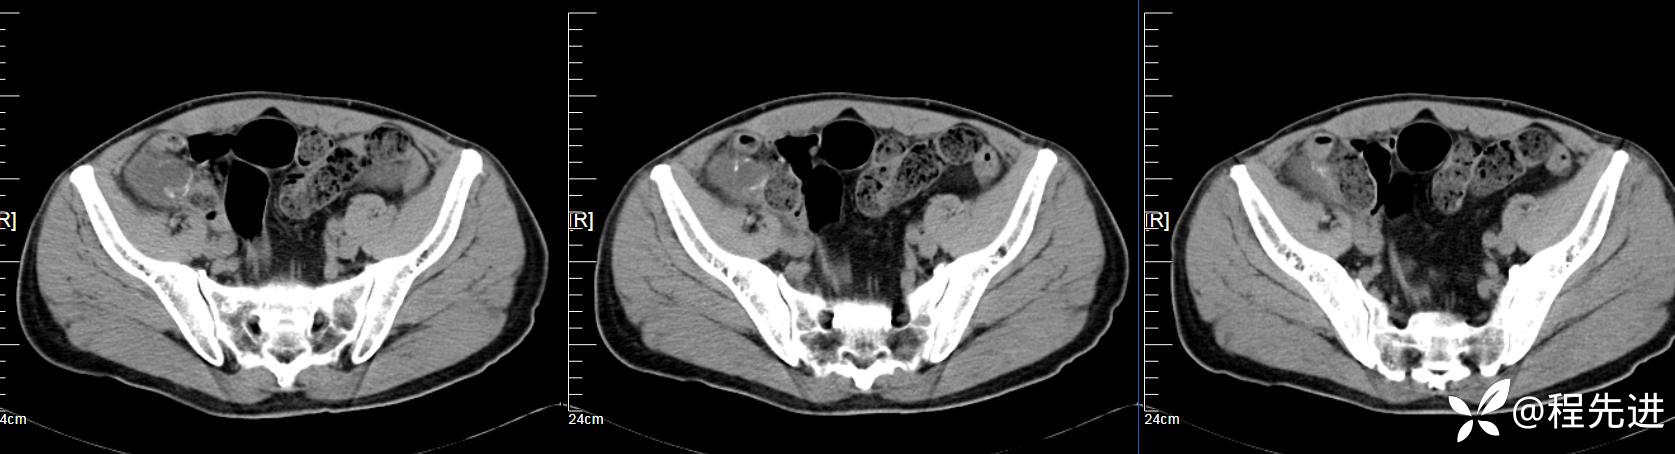

【患者信息】:男,61岁

【现病史及既往史】:右下腹部疼痛伴腹胀2天

【影像检查】